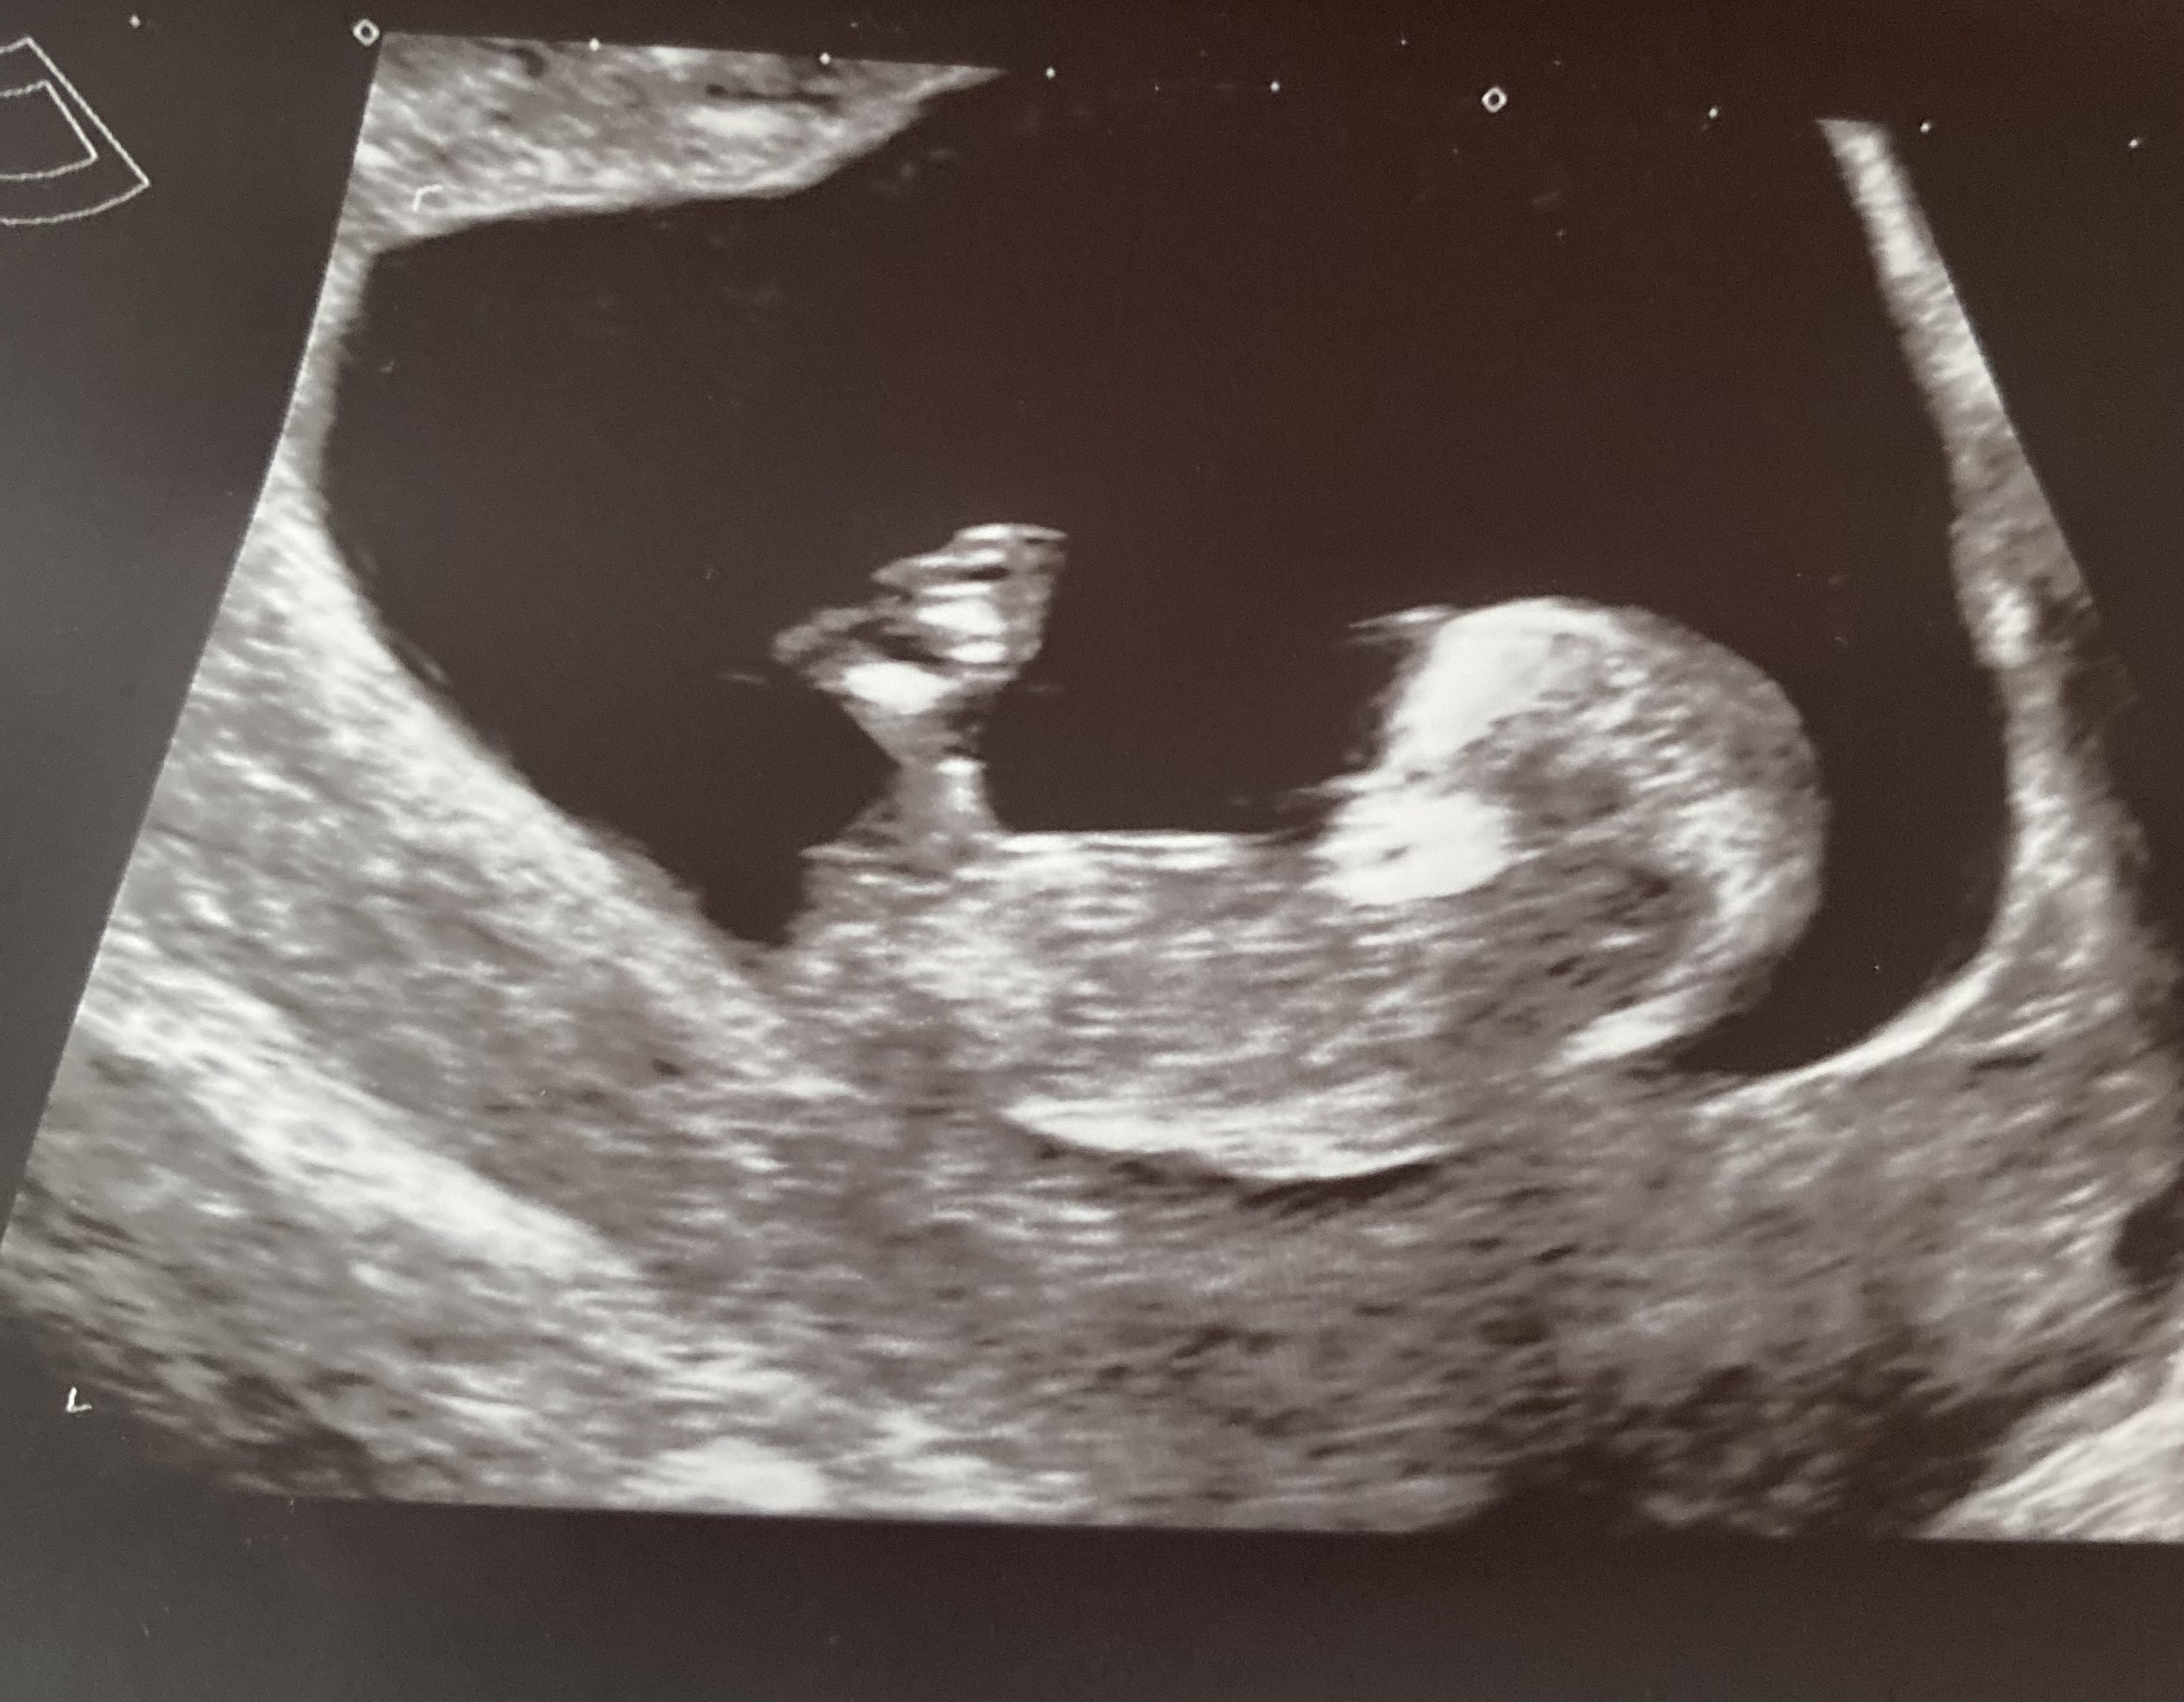

NieHej dziewczyny czy waszym zdaniem tu już widać płeć dziecka czy jeszcze nie 11 tc